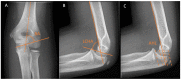

Osseous deformities in children arise due to progressive angular growth or complete physeal arrest. Clinical and radiological alignment measurements help to provide an impression of the deformity, which can be corrected using guided growth techniques. However, little is known about timing and techniques for the upper extremity. Treatment options for deformity correction include monitoring of the deformity, (hemi-)epiphysiodesis, physeal bar resection, and correction osteotomy. Treatment is dependent on the extent and location of the deformity, physeal involvement, presence of a physeal bar, patient age, and predicted length inequality at skeletal maturity. An accurate estimation of the projected limb or bone length inequality is crucial for optimal timing of the intervention. The Paley multiplier method remains the most accurate and simple method for calculating limb growth. While the multiplier method is accurate for calculating growth prior to the growth spurt, measuring peak height velocity (PHV) is superior to chronological age after the onset of the growth spurt. PHV is closely related to skeletal age in children. The Sauvegrain method of skeletal age assessment using elbow radiographs is possibly a simpler and more reliable method than the method by Greulich and Pyle using hand radiographs. PHV-derived multipliers need to be developed for the Sauvegrain method for a more accurate calculation of limb growth during the growth spurt. This paper provides a review of the current literature on the clinical and radiological evaluation of normal upper extremity alignment and aims to provide state-of-the-art directions on deformity evaluation, treatment options, and optimal timing of these options during growth.